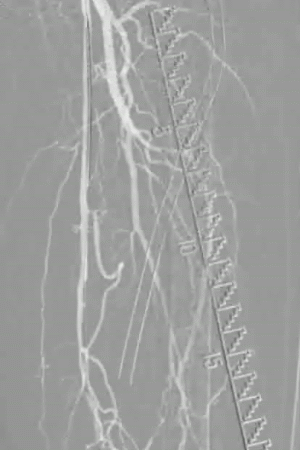

图片图片图片

手术策略:DA+DCB

手术过程(一):

先使用小球囊预扩张、随后将NAV6保护伞置于腘动脉远端,使用TurboHawk LX-M斑块旋切装置对股浅动脉病变处进行多点旋切。

图片